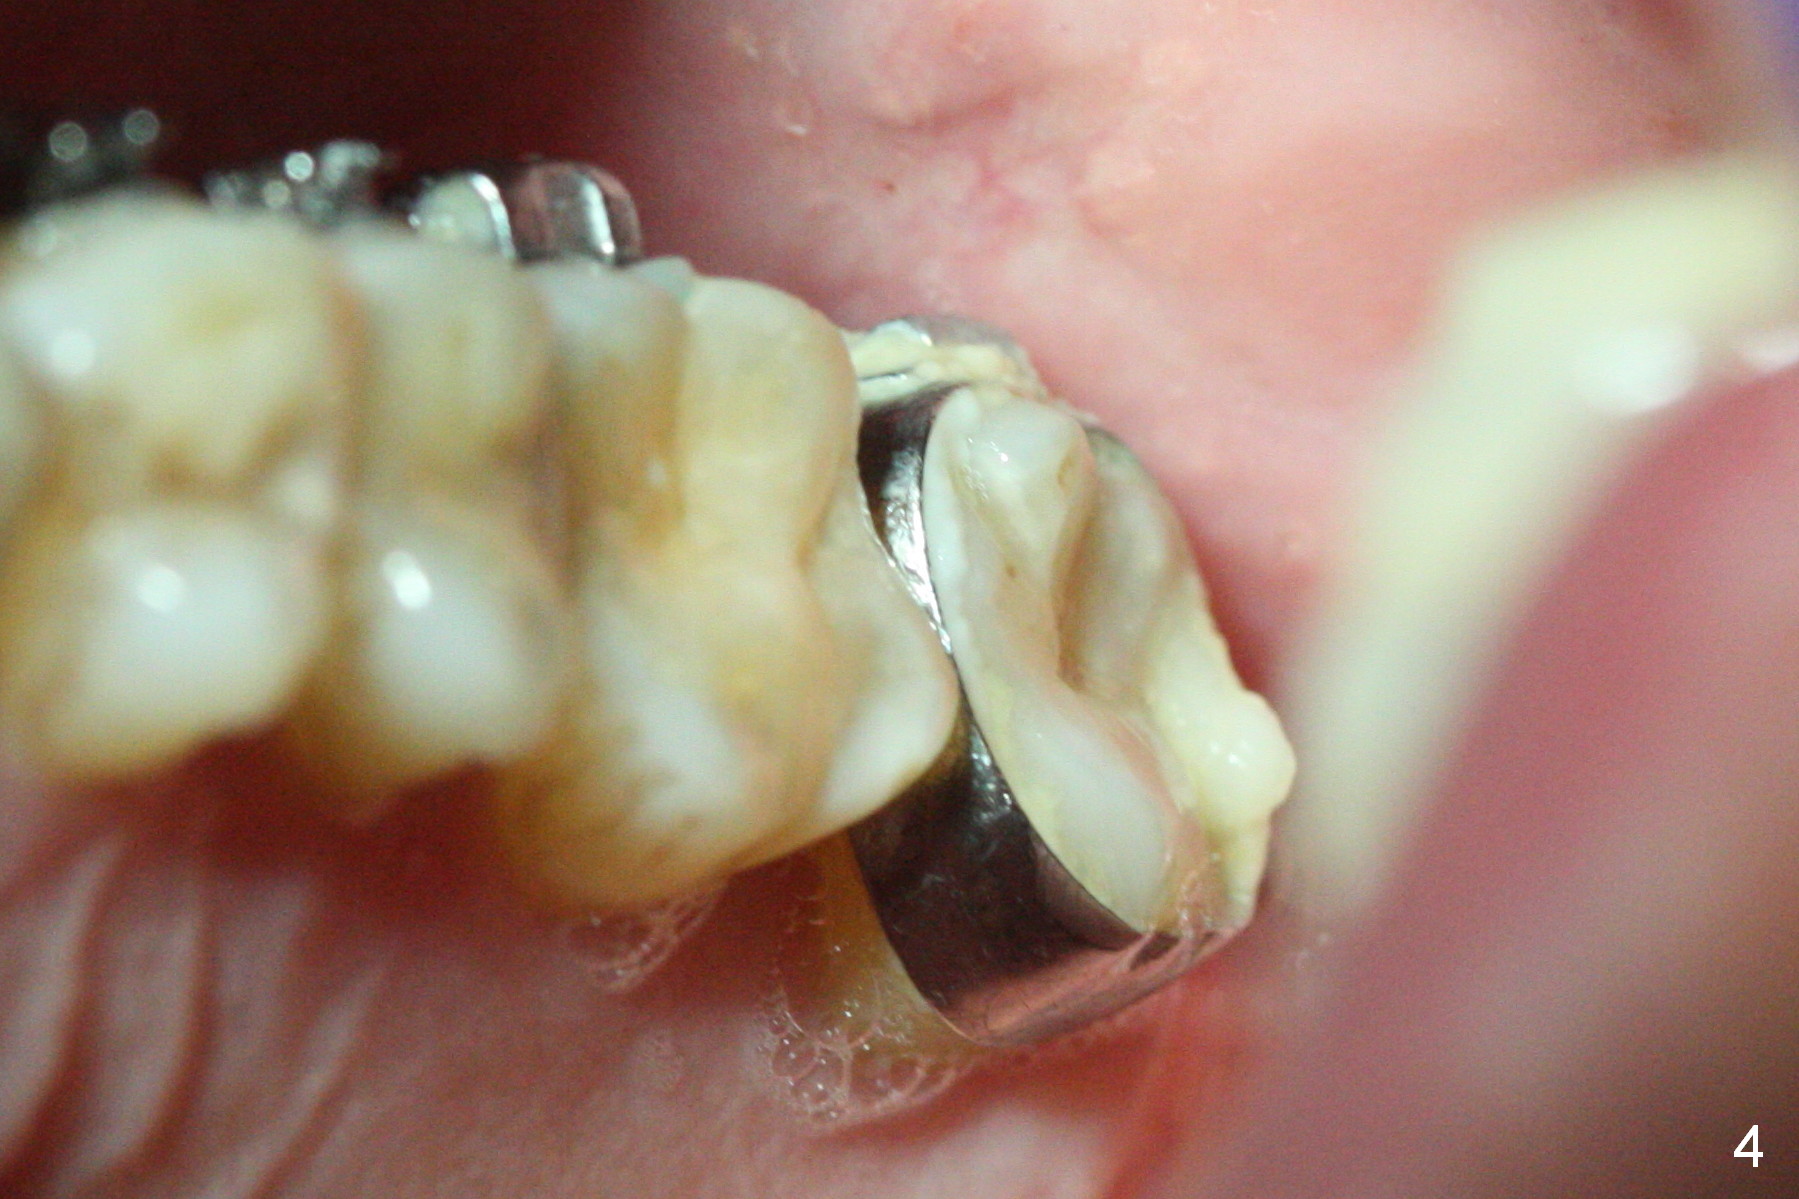

A 50-year-old man has lost the tooth #18 for 10 years; the opposing tooth (#15) has been supraerupted in the last 6 years (Fig.1,2). Mini-implants are placed to intrude the tooth #15 (Fig.2 arrow), instead leading to distalization in 4 months (Fig.3 arrow). Segmental orthodontic appliances are placed with noncompliance. Five months post implant placement at #18, a provisional (Fig.5 P) is fabricated with intentional supraocclusion. In 4 months, the marginal ridges of the teeth #14 and 15 are at the same level (Fig.4). To prevent the 2nd molar from distalization, keep the third molar if present.